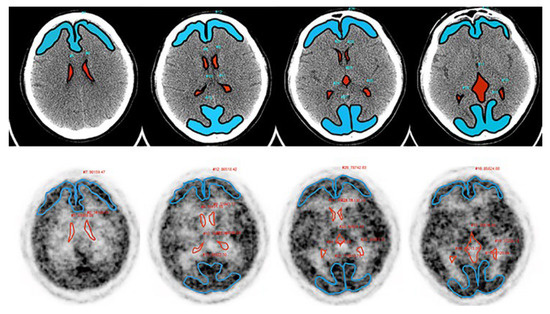

A 1000-MBq [15O]H2O synthesized online was injected intravenously using an automatic water injection system, followed immediately by a 10-mL saline flush at the speed of 1 mL/s (AM WR01; JFE Technos, Yokohama, Japan). After starting the injection, PET emission data were promptly acquired over 20 min in three-dimensional list mode with a 25.6-cm axial FOV and sorted into 47-time frames (18 × 10 s, 24 × 30 s, 5 × 60 s). The CT and PET image data were transferred to a Xeleris 3.1 workstation (GE Healthcare) for PET data analysis. Manually defined ROIs (lateral and third ventricles, cortex of the frontal and occipital lobes) utilizing CT and [15O]H2O PET images were drawn using volumetrix MI on a Xeleris 3.1 workstation (Figure 2).

Figure 2. The ROIs for analyzing the interstitial water flow were defined utilizing CT (upper) and [15O]H2O PET (lower) images on a Xeleris 3.1 workstation. [15O]H2O PET images in 60–120 s after the administration were reconstructed to confirm the cortex, which had high uptake regions. Blue areas: frontal and occipital cortex. Red areas: lateral and third ventricle.